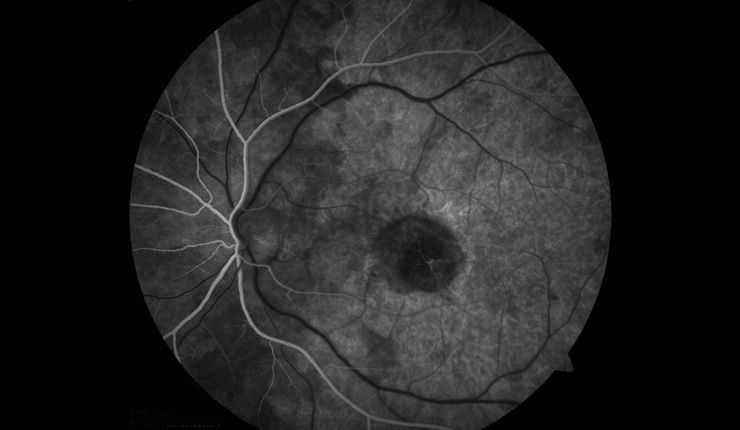

Corresponding topographic thickness map of fundus region highlighting shallow fluid temporal to the disc at the left hand side of the image (central blue/green area represents the fovea).